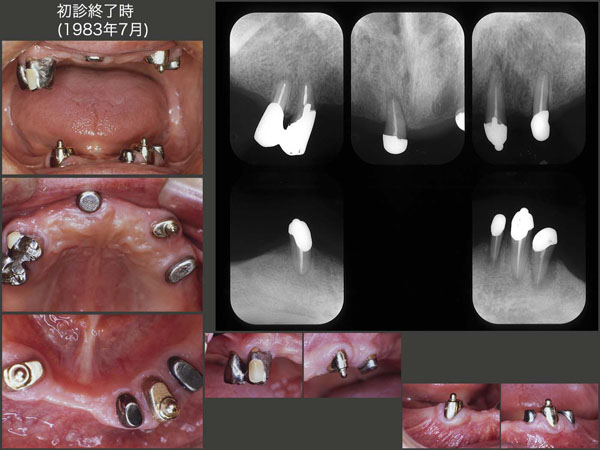

スライドは,83年7月,初診終了時の義歯装着時の状態.今になって見返すと,この時の咬合高径が高いのではないか?と思えるが,当時は全く頭をよぎらなかった.なお,この件に関しては,あとのスライド9でもう一度検討する.

右上4,5は連結冠,左上3,右下3,左下3にBona 604A根面アタッチメント,右上1,左上5および左下2,4に根面板をそれぞれ装着した.なお当時は,私自身が歯科技工を行った.